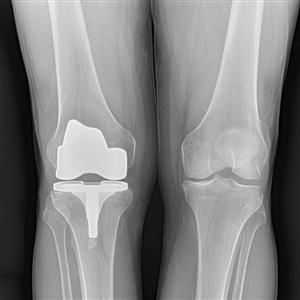

Digital X.Rays = High Resolution very precise x.ray images on laser films produced with the help of computers and High end laser X-Ray Film printers.

It gives more precise and better quality x.rays in shorter period as compared to the routine conventional x.ray films.